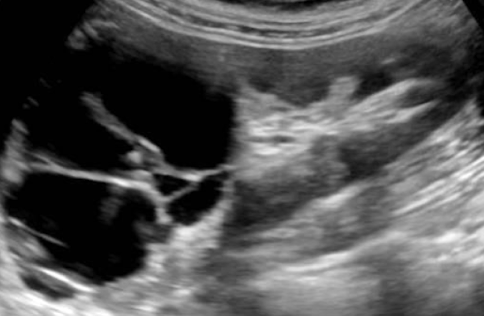

??

complex cyst

has septations and solid components